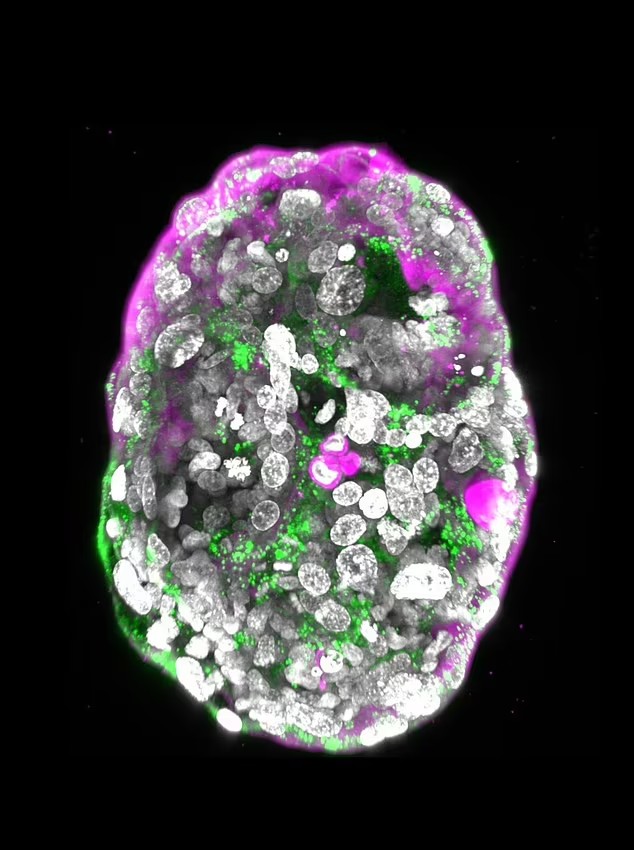

دانشمندان برای اولین بار در جهان توانستند مدل جنین مصنوعی را بدون استفاده از اسپرم، تخمک یا رحم رشد دهند. جنین حتی مقدار کافی از هورمونی را که تست بارداری زنان را مثبت می کند را آزاد کرده است. محققان موسسه علوم وایزمن (Weizmann) در اسرائیل مدل های کاملی از جنین انسان را از سلول های بنیادی تولید شده در آزمایشگاه، ساختند. هدف پژوهشگران این است که بتوانند از نظر اخلاقی آنچه را که در مراحل اولیه بارداری اتفاق می‌افتد، بدون آزمایش روی جنین‌های واقعی انسان مطالعه کنند. مدل توسعه یافته توسط این تیم، مجموعه ای از سلول هاست که به انسان تبدیل نمی شوند.

در حقیقت این جنین انسان نیست و نمی تواند تبدیل به انسان شود، زیرا جنین مصنوعی نمی تواند با موفقیت در دیواره رحم کاشته شود. این مدل جنین مصنوعی، دارای تمام عناصری بود که انتظار می رفت یک جنین ۱۴ روزه انسان از جمله جفت، کیسه زرده، غشاها و سایر بافت های خارجی داشته باشد.

از مواد شیمیایی برای تشویق این سلول‌های بنیادی برای تبدیل شدن به چهار نوع سلول مورد نیاز برای ساخت جنین استفاده شد. حدود ۱۲۰ سلول در یک نسبت دقیق با هم مخلوط شدند که در کل حدود ۰.۰۱ میلی متر اندازه داشت. در روز چهاردهم، تنها یک درصد از این ترکیب سلولی به طور خود به خود به حدود ۲,۵۰۰ سلول تکثیر شد و اندازه آن به ۰.۵ میلیمتر رسید. با این حال، ۹۹ درصد دیگر رشد نکردند.